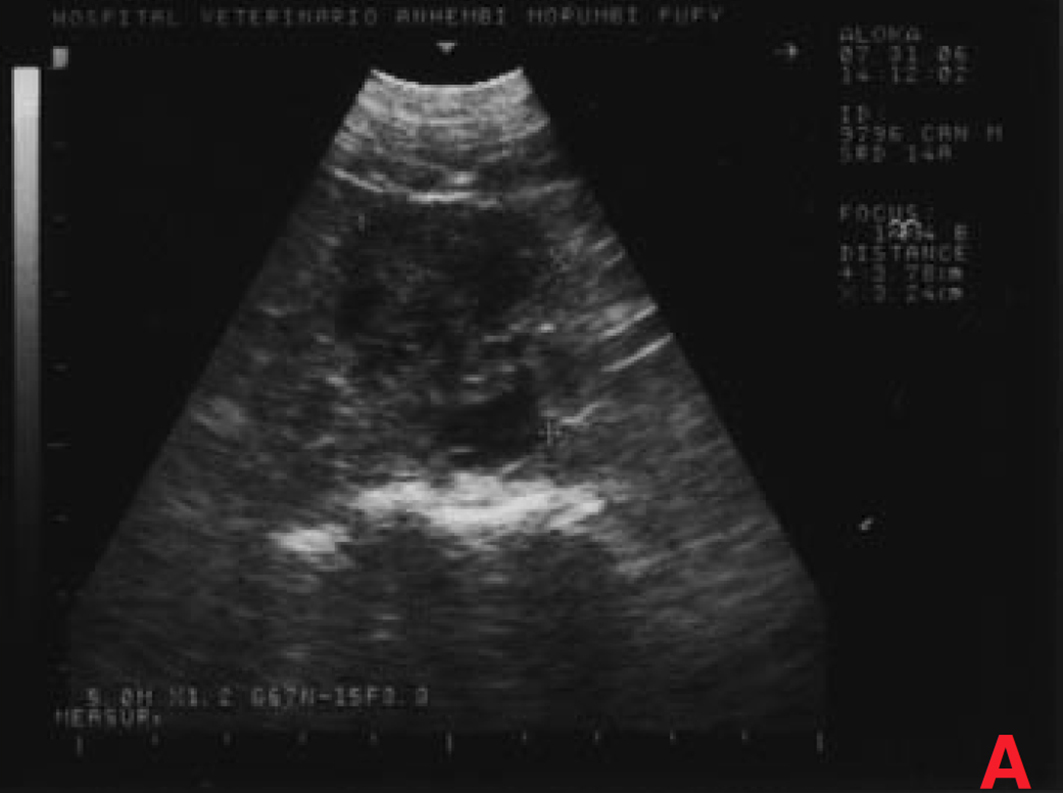

Não houve alterações na avaliação hematológica, na bioquímica (creatinina, ureia) e na radiografia torácica, porém o exame ultrassonográfico mostrou aumento de próstata (4,3 x 3,8 x 2,8cm), com áreas císticas difusas pelo parênquima (imagens sugestivas de hiperplasia prostática benigna/prostatite); somente um testículo em bolsa escrotal; grande aumento de volume em região inguinal esquerda (formação heterogênea em ecotextura e ecogenicidade) e aumento de cadeia de linfonodos sublombares e ilíacos (medindo até 2,4 x 1,6cm, com ecogenicidade e ecotextura heterogêneas) (Figura 3).

Após vinte dias, o estado do animal era bom. Realizou-se então um exame ultrassonográfico de controle, através do qual se observou que o volume da próstata continuava crescendo e que os linfonodos sublombares e ilíacos tinham aumentado, passando a medir 5 x 3,8 x 3,2cm, com ecogenicidade e ecotextura heterogêneas, devendo-se considerar a possibilidade de processo metastático.

O exame ultrassonográfico demonstrou aumento de próstata mais acentuado (6 x 5 x 5,6 cm), com áreas císticas/cavitárias difusas pelo parênquima (sugestivas de hiperplasia prostática benigna/prostatite/neoplasia) e aumento de cadeia de linfonodos sublombares e ilíacos (5 x 4,6 x 4 cm), com ecogenicidade e ecotextura heterogêneas, sugestivo de processo metastático (Figura 9).